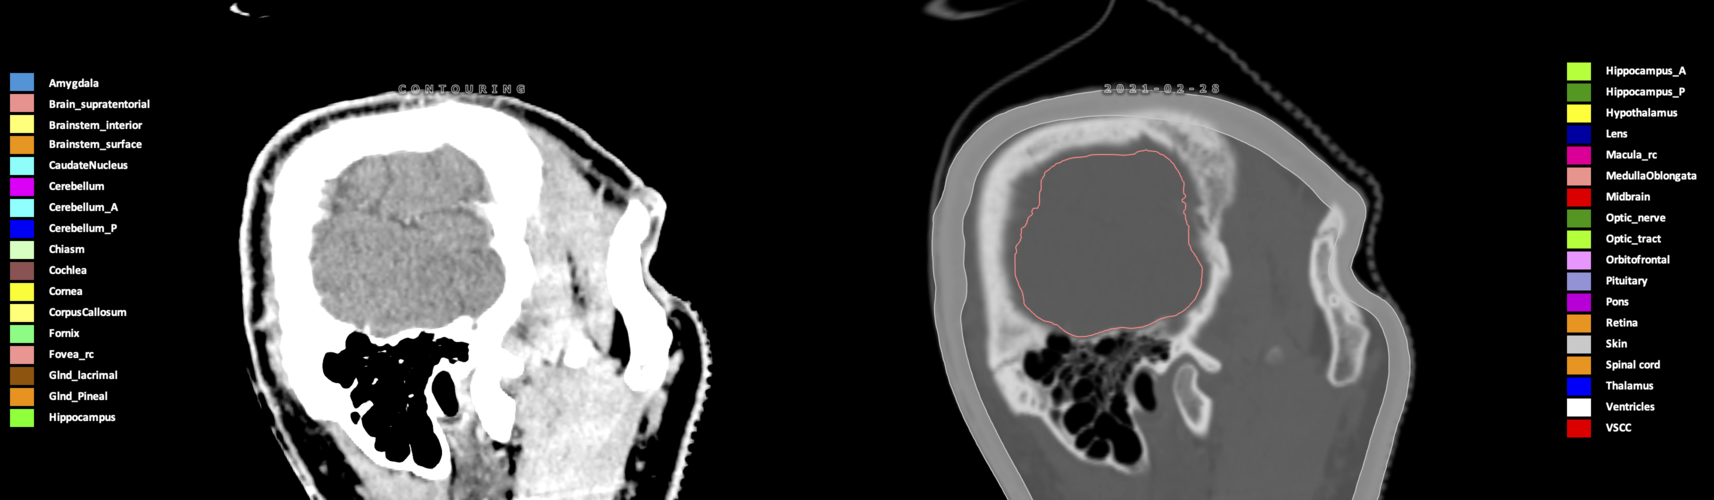

Included are all OARs known to be relevant for radiation-induced toxicity in neuro-oncology: brain, brainstem (midbrain, pons, medulla oblongata), chiasm, cerebellum (anterior & posterior), cochlea, cornea, hippocampus (anterior & posterior), hypothalamus, lens, lacrimal gland, optic nerve, pituitary, skin, and vestibular & semicircular canals. To further facilitate research on cognition, vision and radiological changes after irradiation of the brain, potential clinically-relevant OARs are included: amygdala, caudate nucleus, cerebellum (anterior & posterior), corpus callosum, fornix, macula, optic tract, orbitofrontal cortex, periventricular space (PVS), pineal gland, and thalamus.

Three-dimensional delineation of the 25 consensus OARs for neuro-oncology are shown on CT (WW/WL 120/40, 3000/600), 3T MR images, (T1Gd, T2FLAIR 1mm) and 7T MR (MP2RAGE 0.7 mm). All are presented in transversal, sagittal and coronal view.